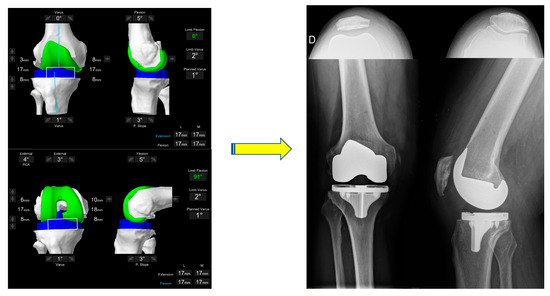

- Coronal plane: femoral implant positioning is planned according to the LDFA with an upper limit of 6° mechanical valgus in femur. To achieve a final alignment with a maximum valgus of 183°, varus positioning on the tibia may be required unless there is extra-articular varus deformity in either the femur or tibia.

- Axial plane: In the valgus morphotype, the posterior lateral femoral condyle is often deficient, making the posterior condylar axis an unreliable landmark for rotation [38]. For this reason, femoral component rotation is planned to balance the flexion space according to the transepicondylar axis (TEA), within a range of 3° internal rotation (IR) to 6° external rotation (ER) to balance the flexion gap. All these adjustments must be made while respecting the alignment with the trochlear groove; care must be taken to assess for trochlea dysplasia which may be present in valgus knees, and if so, recreation of the dysplastic anatomy, such as internally rotating the femur relative to the posterior condylar axis (PCA), should be avoided.

- Coronal plane: tibial implant position is aligned to provide the closest match to the medial proximal tibial axis (MPTA) and balance flexion and extension gaps in a range from 2° of valgus to 6° of varus. In the valgus morphotype, in order to avoid a residual valgus HKA > 3° valgus, the tibia is often cut orthogonal to its mechanical axis. A valgus tibial position more than 2° should be avoided. Valgus tibial positioning is reserved for cases where the deformity is an extra-articular tibial deformity, which in our experience is uncommon.

- Sagittal plane: tibial implant position is set to match the patient’s native posterior tibial slope with a limit of 3° when using a PS implant and can be modified to balance the flexion gap if necessary. A limit of 10° combined femoral-tibial flexion is allowed.

- Tibial resection: 8 mm resection is planned from the medial tibial plateau (6 mm bone + 2 mm cartilage) based on subchondral bone and an average cartilage depth of 2 mm in the normal knee, to use a 9 mm polyethylene insert. Resection from lateral tibial plateau is, typically less i.e., 4–6mm due to wear, but also to account for the extra articular tibial valgus deformity that often co-exists in the valgus morphotype [31]. This gives a combined planned resection of 17 mm medially, which is the combined thickness of this implant with its thinnest tibial liner.